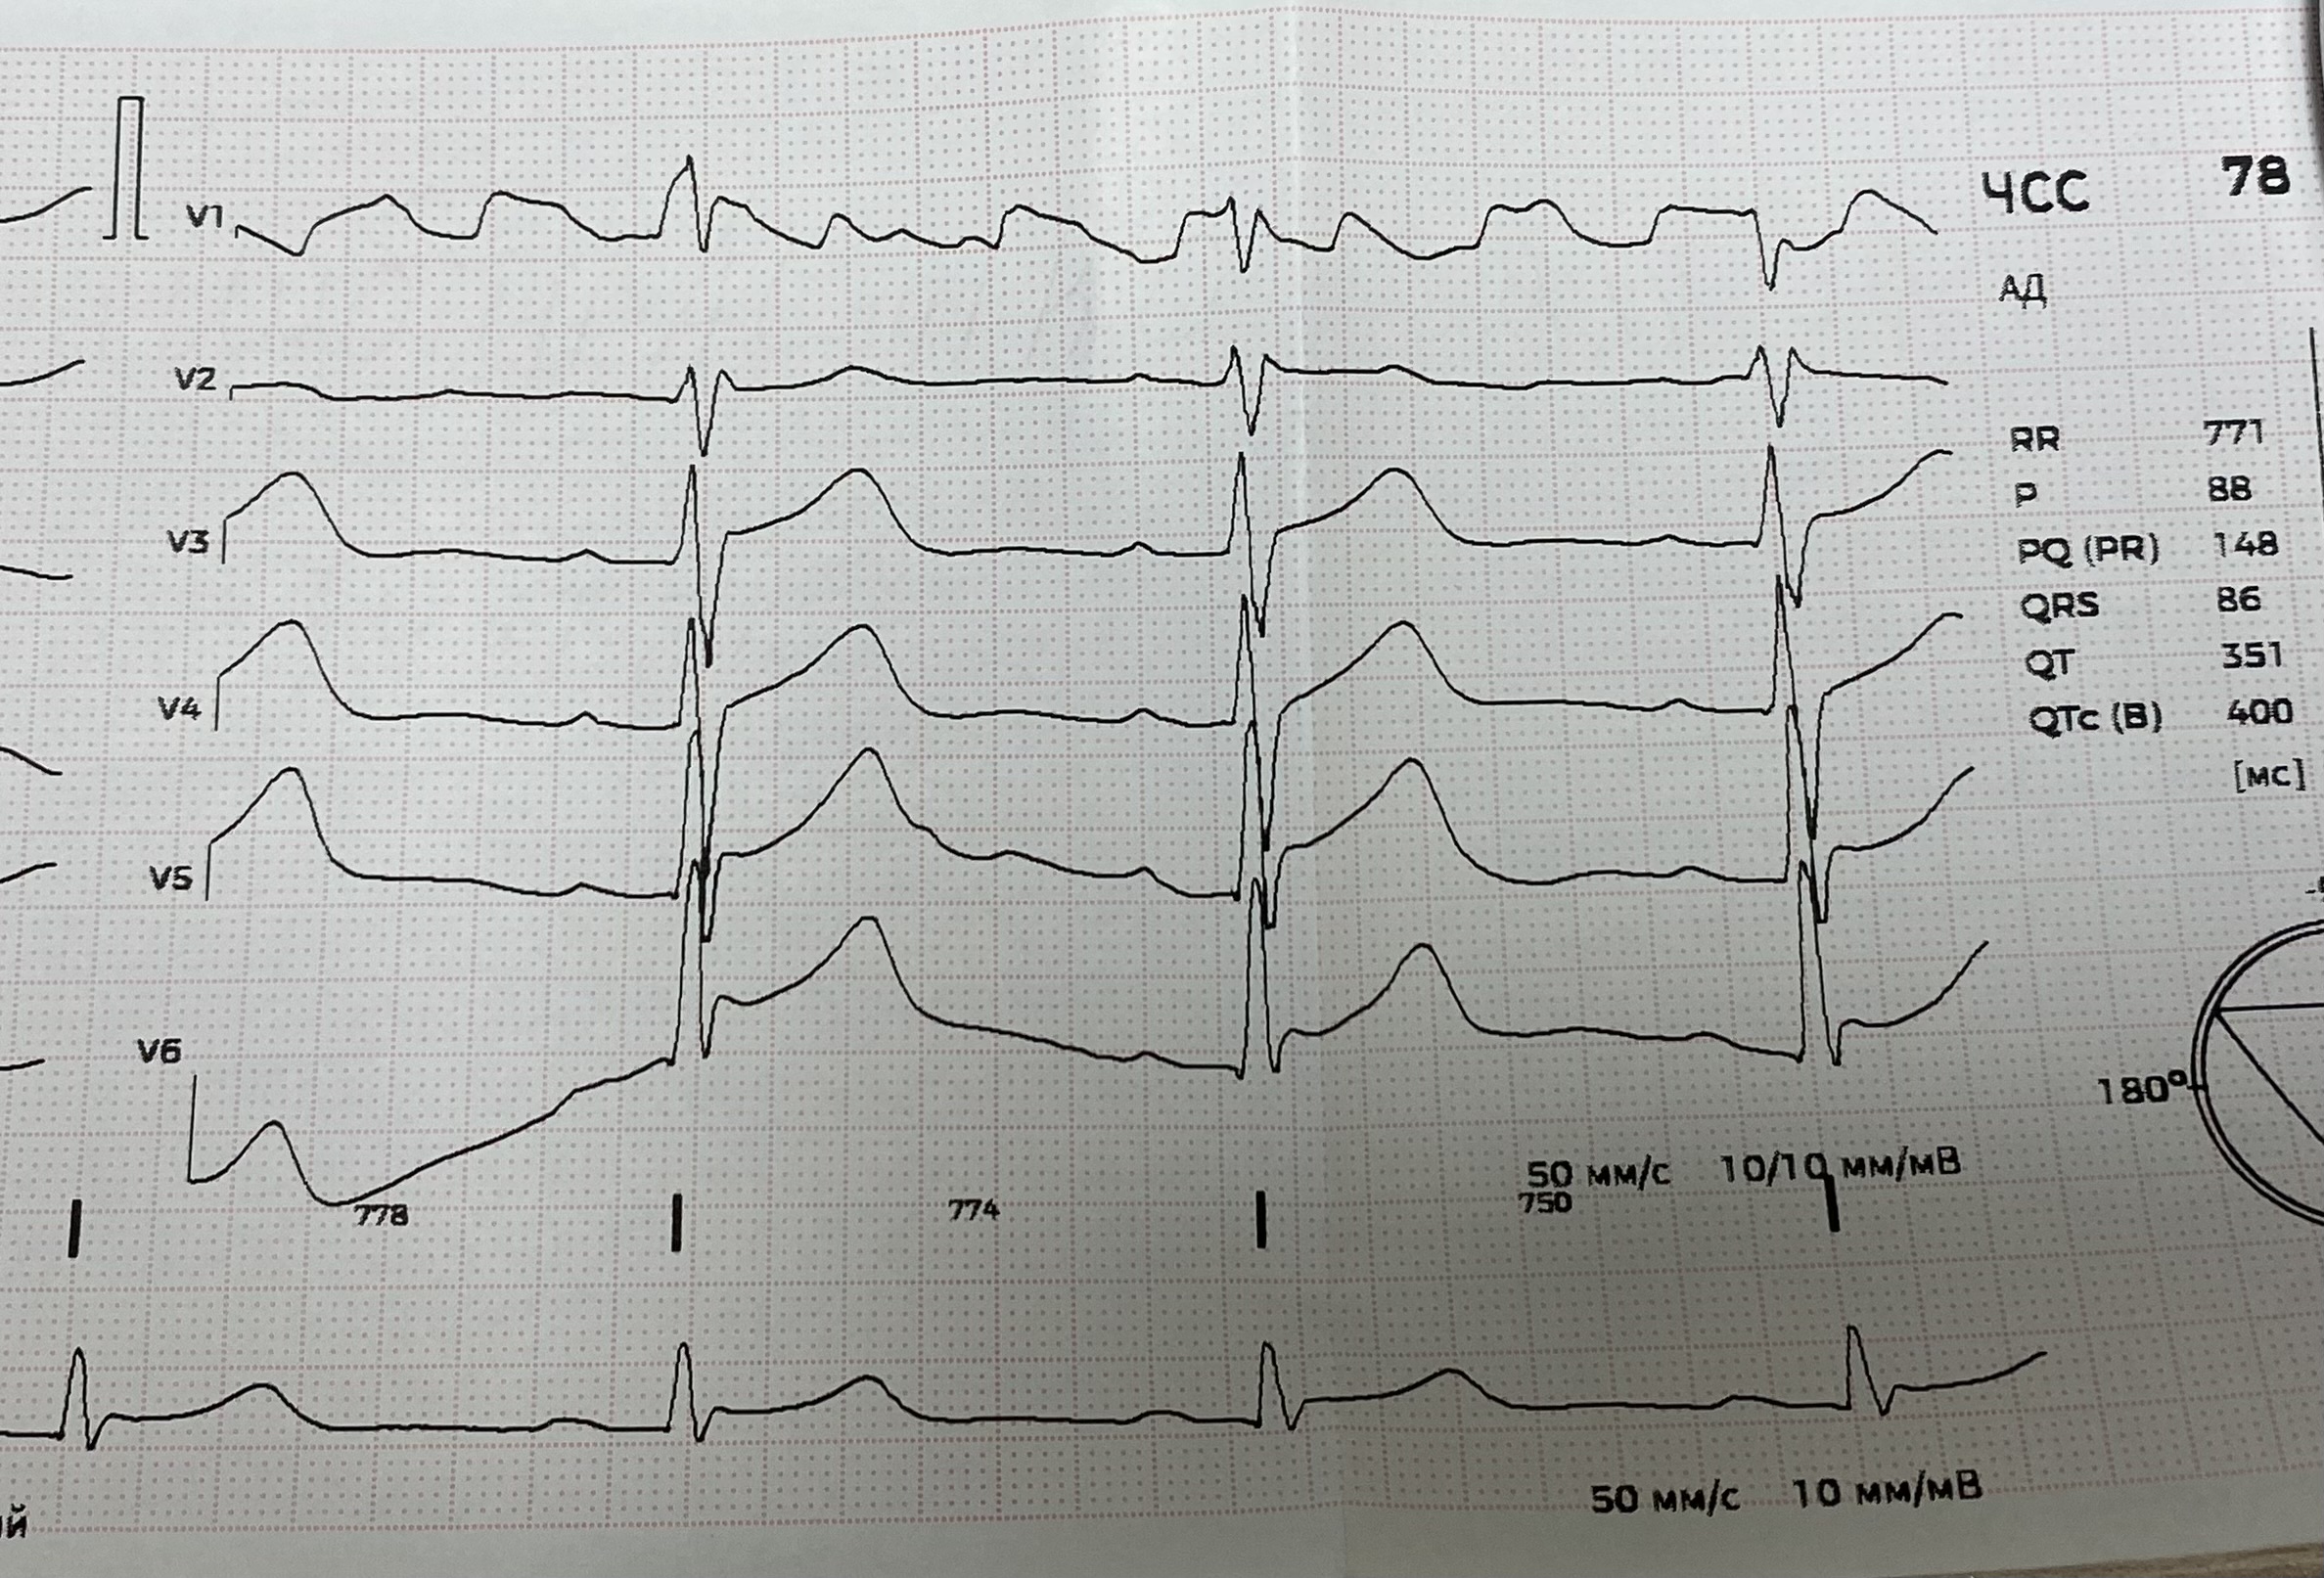

Динамика ЭКГ при гемоперикарде. До и после удаления крови.

Вложения:

IMG_8524.jpg

IMG_8524.jpg [ 2.78 MiB | Просмотров: 1850 ]

IMG_8525.jpg

IMG_8525.jpg [ 3.22 MiB | Просмотров: 1850 ]

IMG_8526.jpg

IMG_8526.jpg [ 2.19 MiB | Просмотров: 1850 ]

IMG_8527.jpg

IMG_8527.jpg [ 2.47 MiB | Просмотров: 1850 ]